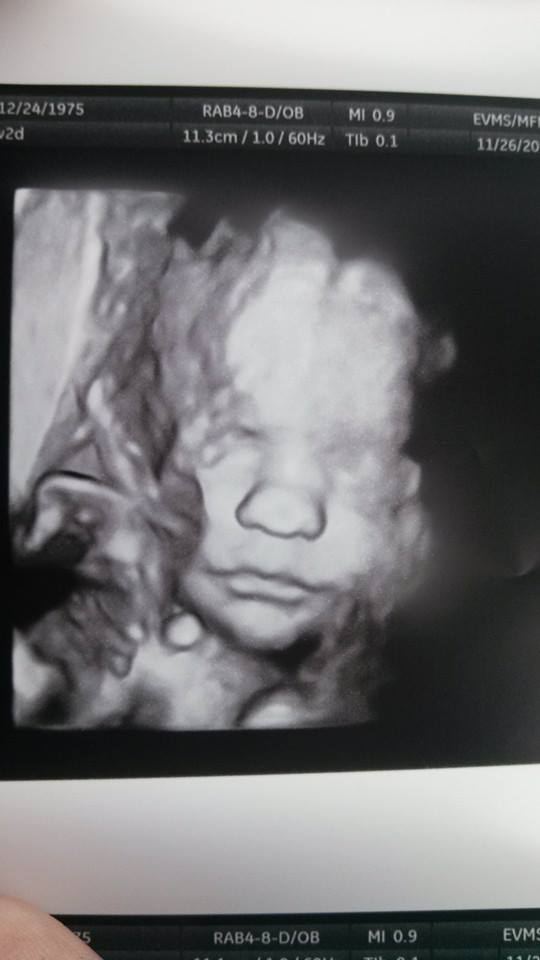

Warning: 3D US pics! Lol. If you don't like em, click away now!

We had ours done today! Here's LO!

Funny story: my mom wanted to know why he was bumpy. I've explained this before to her, I think she thinks I'm having a bumpy baby.